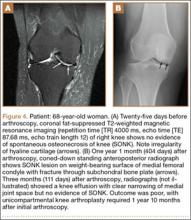

Table 1 lists the demographics and imaging characteristics of the 11 patients—6 had SONK before arthroscopy and 6 developed it after arthroscopy. Comparison of the 11 patients with SONK and the 11 controls is summarized with P values in Table 2. Representative cases that either presented before surgery or developed after surgery are shown in Figures 1 to 4. There were 6 prearthroscopy lesions and 6 postarthroscopy lesions—all 12 in the medial femoral condyle. Eleven of the 12 knees had a medial meniscal tear, and 1 knee had both medial and lateral meniscal tears. In 8 of the 12 knees, the lateral meniscus was normal; in 2 knees, it had mild degeneration; and, in 1 knee, it had a complex tear. Assessment of hyaline cartilage revealed medial cartilage loss ranging from 2A to 3B (median, 2B) in the patients with SONK, and lateral cartilage loss ranging from 0 to 2A (median, 0). At surgery, all knees had a partial medial meniscectomy, and 6 had a partial lateral meniscectomy. Ten of the 12 knees had chondroplasty, 9 patellar and 5 of the medial femoral condyle. Only 4 of the 11 patients with follow-up of more than 1 year went on to joint replacement. Six of the 12 had follow-up of more than 2 years. Of the 6 patients without an identifiable SONK lesion on MRI before arthroscopy, 4 had mild to moderate knee pain 0.5, 2.4, 3.5, and 4 years after surgery. For the other 2 patients, knee replacement was performed 1.5 and 1.8 years after surgery. Of the 6 patients with prearthroscopy SONK, 4 had mild to moderate knee pain 1.5, 3.7, 6.5, and 6.8 years after surgery; the other 2 had knee replacement 0.5 and 1.8 years after surgery. Articular cartilage degeneration and meniscal extrusion were similar (Table 1). In the control group, there was only 1 knee replacement, at 3 years, and the other 11 were functioning 2.6 to 5 years later. The longer follow-up resulted from selection of appropriate controls from the same year. Of the 6 SONK lesions found on preoperative MRI, 3 were read by the interpreting radiologist before surgery as possible SONK lesions, 2 were read as insufficiency fractures, and 1 was read as a possible insufficiency fracture.